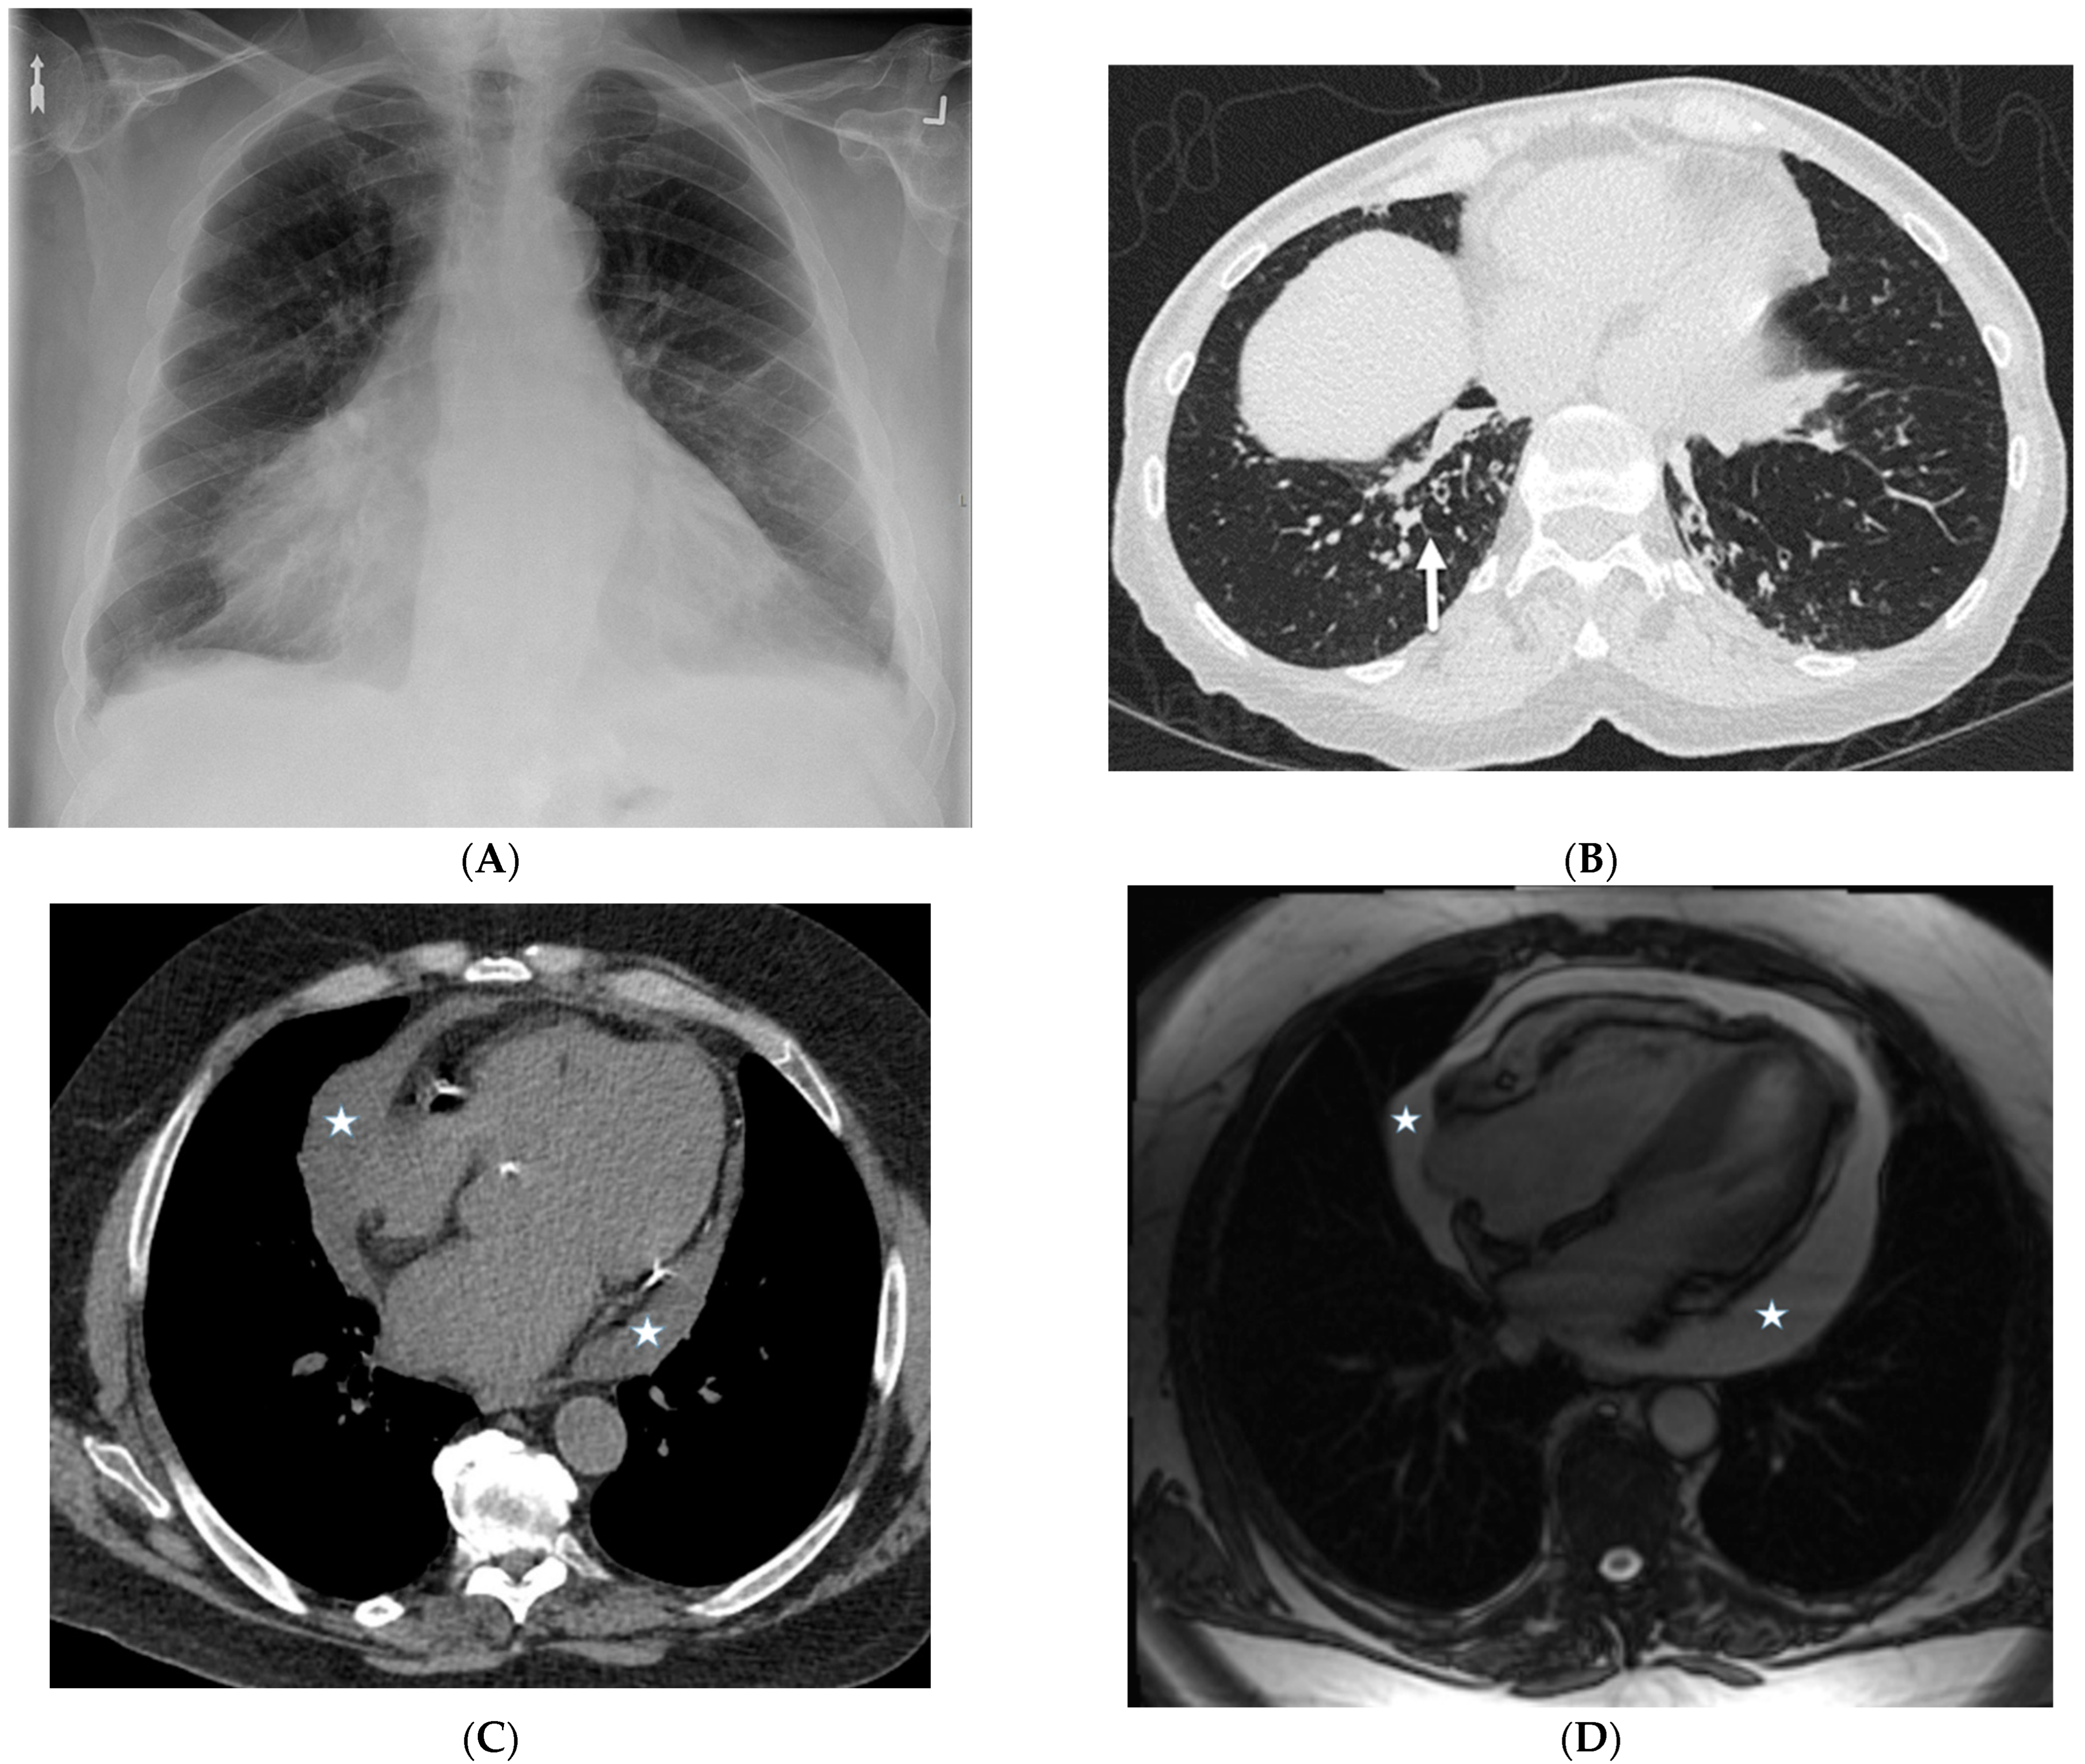

8.4. Erdheim Chester Disease (ECD)

8.5. Niemann–Pick Disease (NPD)